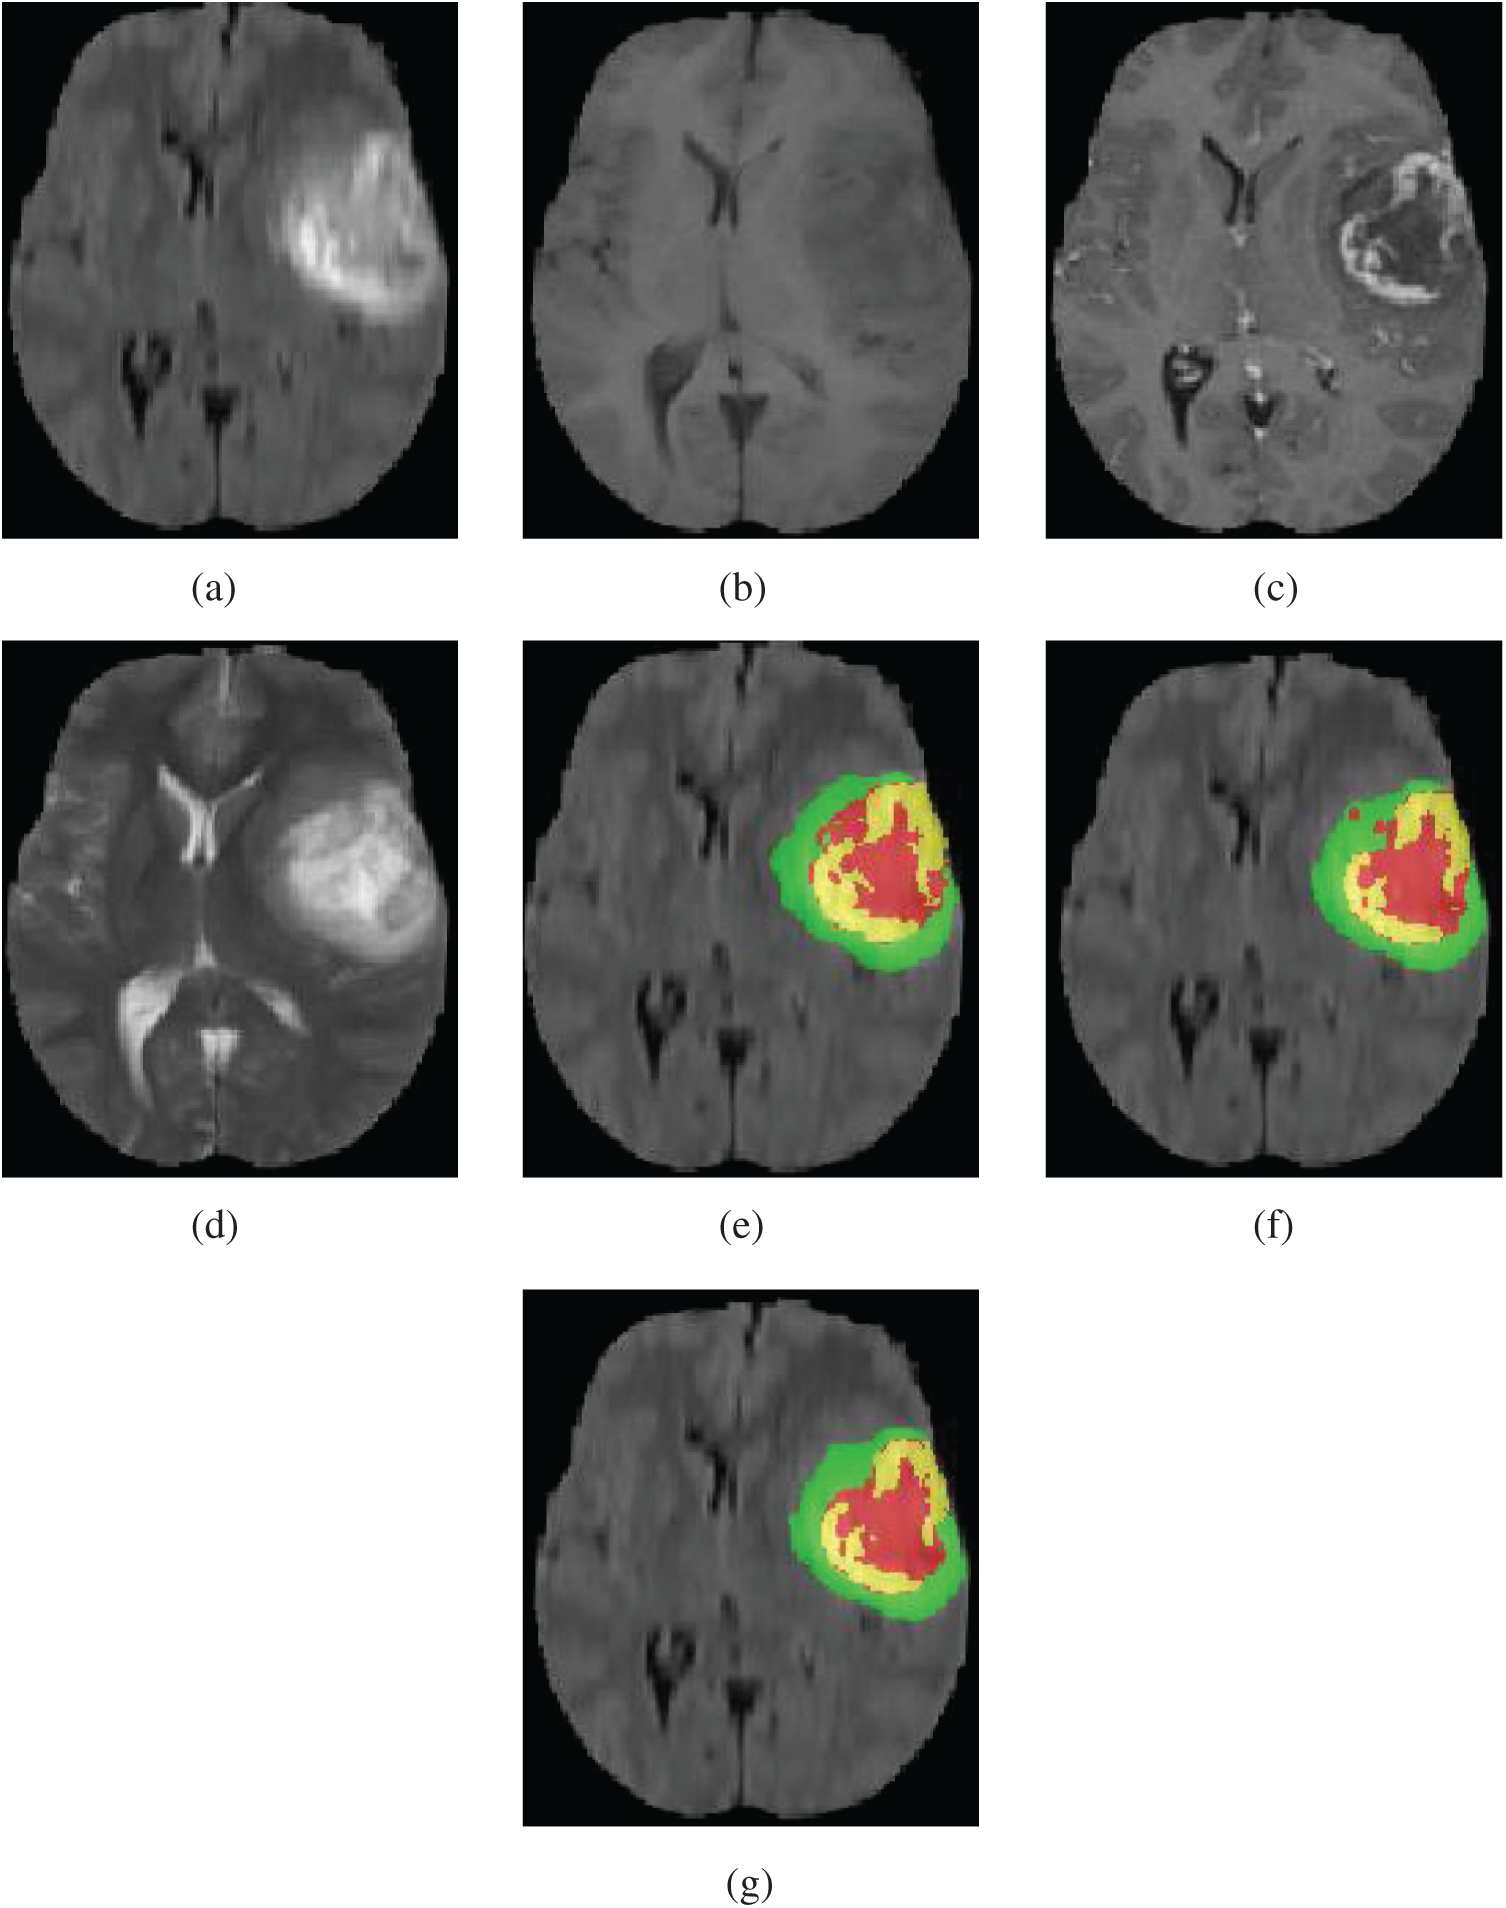

Our method was qualitatively compared with original 3D U-Net. We randomly selected a patient and used both our method and original 3D U-Net to segment the brain tumor. Fig. 5 shows slices of the four modalities, the ground truth of the patient named “BraTS19_2013_21_1,” and the slices of the predicted segmentation image using our method and original 3D U-Net.

Figure 5: Four modalities axial slices, ground truth and segmentation results of a patient from Brats2019 training dataset using our network and original 3D U-Net. Yellow indicates enhancing tumor core, green indicates edema, red indicates necrotic and non-enhancing tumor core in (e), (f) and (g). (a) FLAIR, (b) T1, (c) T1Gd, (d) T2, (e) Ground truth, (f) original 3D U-Net, (g) our network